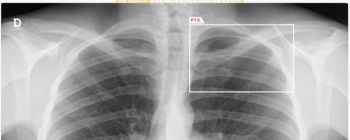

The AI-powered AZchest CXR software reportedly offers 93.79 percent sensitivity and a 98.57 percent AUC for pneumothorax.

Adjunctive use of the AI-powered software led to an average 38.6 percent increase in the detection of pneumothorax by general radiologists, according to a 2023 study.